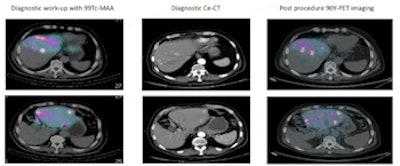

Example on how hybrid imaging modalities can be used successfully to guide liver cancer therapy with radioactive particles. Hybrid imaging can evaluate the feasibility of the therapy and then to assess the correct bio-distribution of the radioactive spheres immediately after the therapy. This is a perfect example on how nuclear medicine and radiology are collaborating not only on the imaging side, but also in performing interventional procedures.